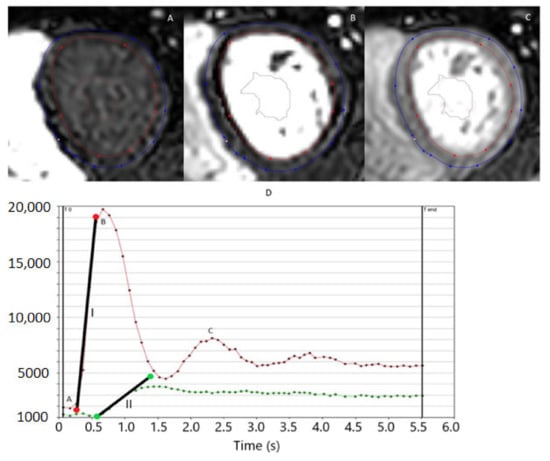

2.4. Myocardial Perfusion